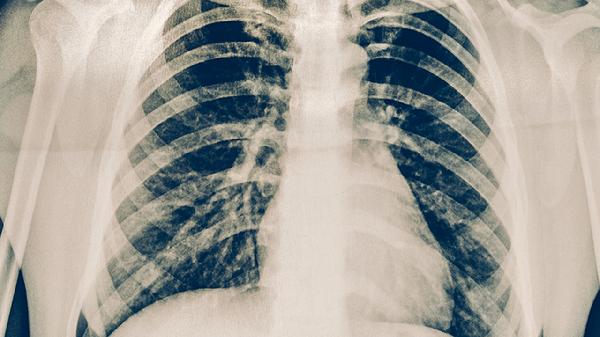

肺结核患者停药后应持续监测症状变化,每3-6个月复查胸部影像学及痰涂片检查。日常需保持均衡饮食,适当补充优质蛋白和维生素,避免过度劳累。居住环境应通风良好,减少与结核病患者的密切接触。若出现疑似复发症状,须立即就医进行痰培养和药敏试验,必要时调整治疗方案。